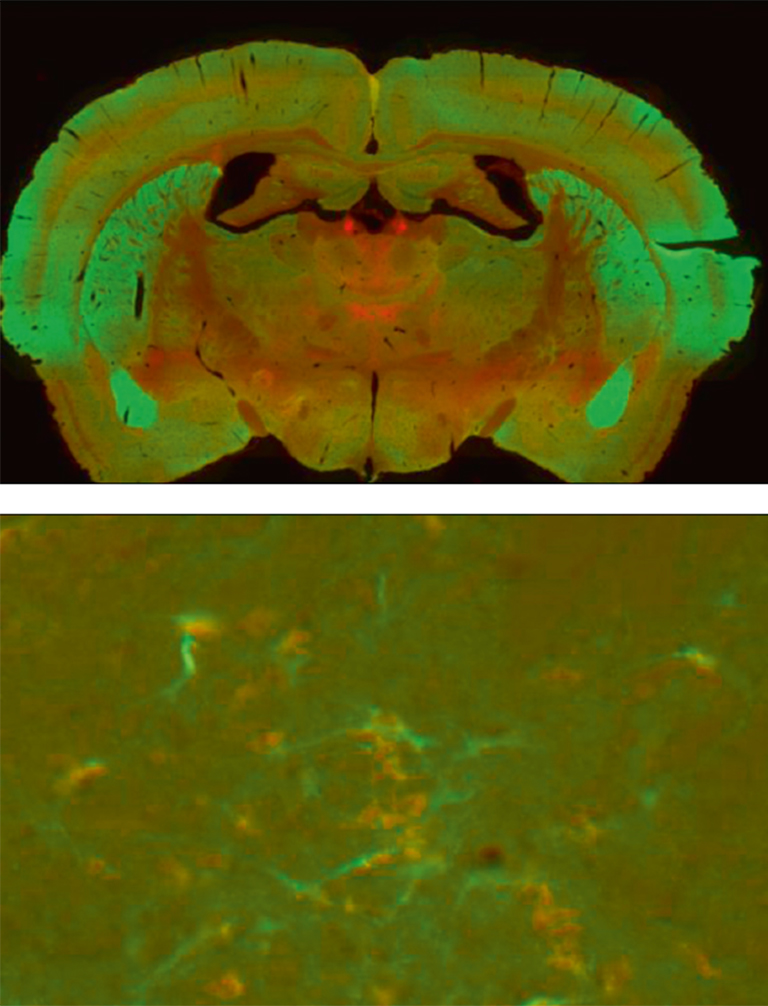

The possibility to optimize image acquisition for each fluorescent probe to take into account its actual intensity represents another major advantage. Combining the bicolor double mutant mouse line and high resolution image acquisition with the Nanozoomer (magnification 40x resolution 0.23 µm/pixel) made then possible to map the two fluorescent receptors throughout the brain and to single out neurons in which the two fluorescent signals were simultaneously present (Figure 2).

Figure 2: Brain coronal section showing the distribution of the fluorescent signals associated to DOR-eGFP (green) and MOR-mcherry (red). General overview (above) and individual neurons (below) using 40x objective.